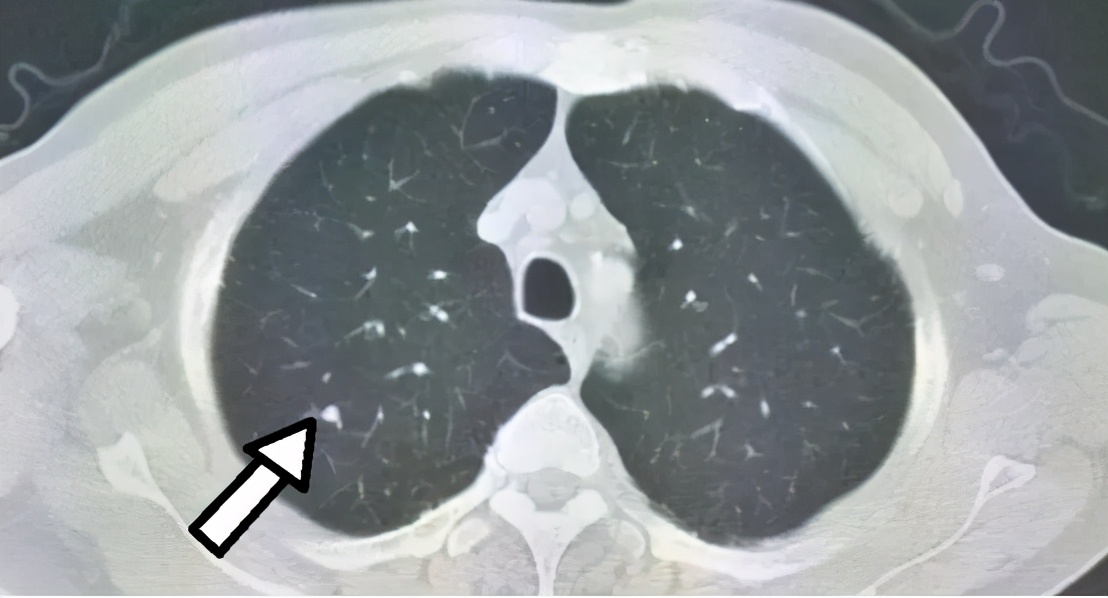

Last week, a patient with a pulmonary nodule came for a consultation. The imaging findings from the chest CT showed a solid nodule measuring approximately 0.5 cm. Based on the imaging, there was a possibility of malignancy, but since it was currently small, the patient was advised to undergo observation. The patient asked, "What if it turns out to be lung cancer? Wouldn't it be better to have surgery sooner?"

Indeed, based solely on the imaging, there is a possibility of malignancy, but it could also be benign. If, after a period of observation, the nodule shrinks, it suggests it may be an inflammatory process. Alternatively, if the nodule remains unchanged over a long period, it is more likely to be benign, thereby avoiding unnecessary surgery.

Even if it were lung cancer, this would not be the optimal time for resection. The lesion is too small, and attempting surgical exploration at this stage might not directly locate the lesion, increasing the difficulty of the procedure and exacerbating the physical harm caused by the surgery.

After explanation, the patient expressed understanding and agreed to undergo CT scans every 3-6 months.

Screening technologies for lung cancer have now become relatively mature. Low-dose chest CT scans can detect lung nodules as small as a few millimeters, enabling the identification of lung cancer lesions at a very early stage.